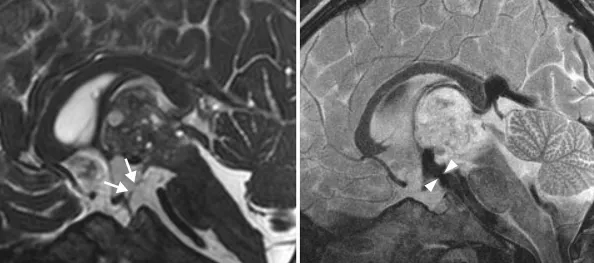

确诊后立即启动治疗方案。医疗团队尝试放置脑室外引流管,并通过脑脊液检测明确诊断为恶性生殖细胞肿瘤。因当地资源有限,KK被转至上级医疗中心,医生首先移除外引流管,实施内镜下第三脑室造瘘术(ETV)及隔膜造口术,成功控制脑积水。然而,原发肿瘤仍构成严重威胁,故迅速给予两个疗程化疗,但影像监测显示肿瘤持续生长,并阻塞双侧室间孔,经多学科讨论后行脑室腹腔分流术作为抢救措施。更令人担忧的是,后续2个月内即使接受大剂量化疗和干细胞移植,肿瘤体积依然增加。

03. 手术全切与长期康复结局